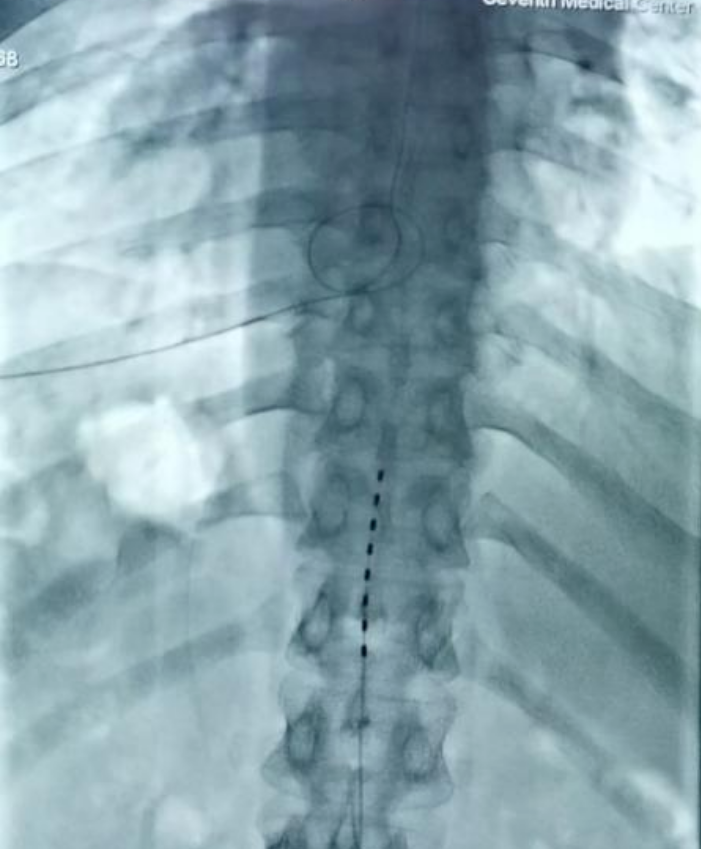

夏主任及其團(tuán)隊(duì)對(duì)患者的病情進(jìn)行了詳細(xì)的評(píng)估,并與患者及家屬充分溝通后,決定實(shí)施脊髓電刺激植入術(shù)。在術(shù)中電生理和術(shù)中影像的引導(dǎo)下,通過(guò)穿刺的技術(shù)將1根柱狀電極精準(zhǔn)放置于T11-T12節(jié)段中線位置。